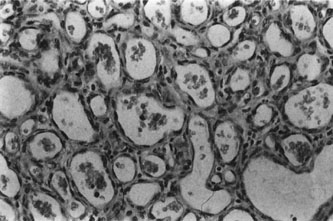

Infantile capillary hemangiomas have a characteristic histopathologic pattern with masses of plump proliferating endothelial cells organized into a network of basement membrane–lined vascular channels with small, irregular lumina (Fig. 4). No true capsule exists.10 A reticulin stain may help delineate primitive vascular structures in early stages of proliferation when there are few vascular spaces.10 During the proliferative phase or for poorly differentiated tumors, the localization of von Willebrand factor produced by the endothelial cells by either peroxidase or fluorescent antibody technique may prove useful.10 Lesions undergoing involution are characterized by fewer endothelial cells, larger and less numerous vascular channels, increasing collagen deposition, intralesional fat, and in some instances, inflammatory cell infiltrates. The late regression phase is dominated by fibrosis.10